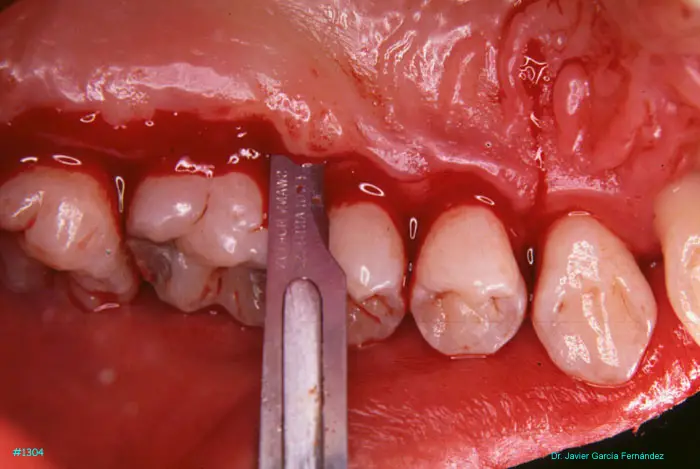

Atlas of Surgical Techniques in Periodontics. Chapter III. Atlas de Técnicas Quirúrgicas en Periodoncia